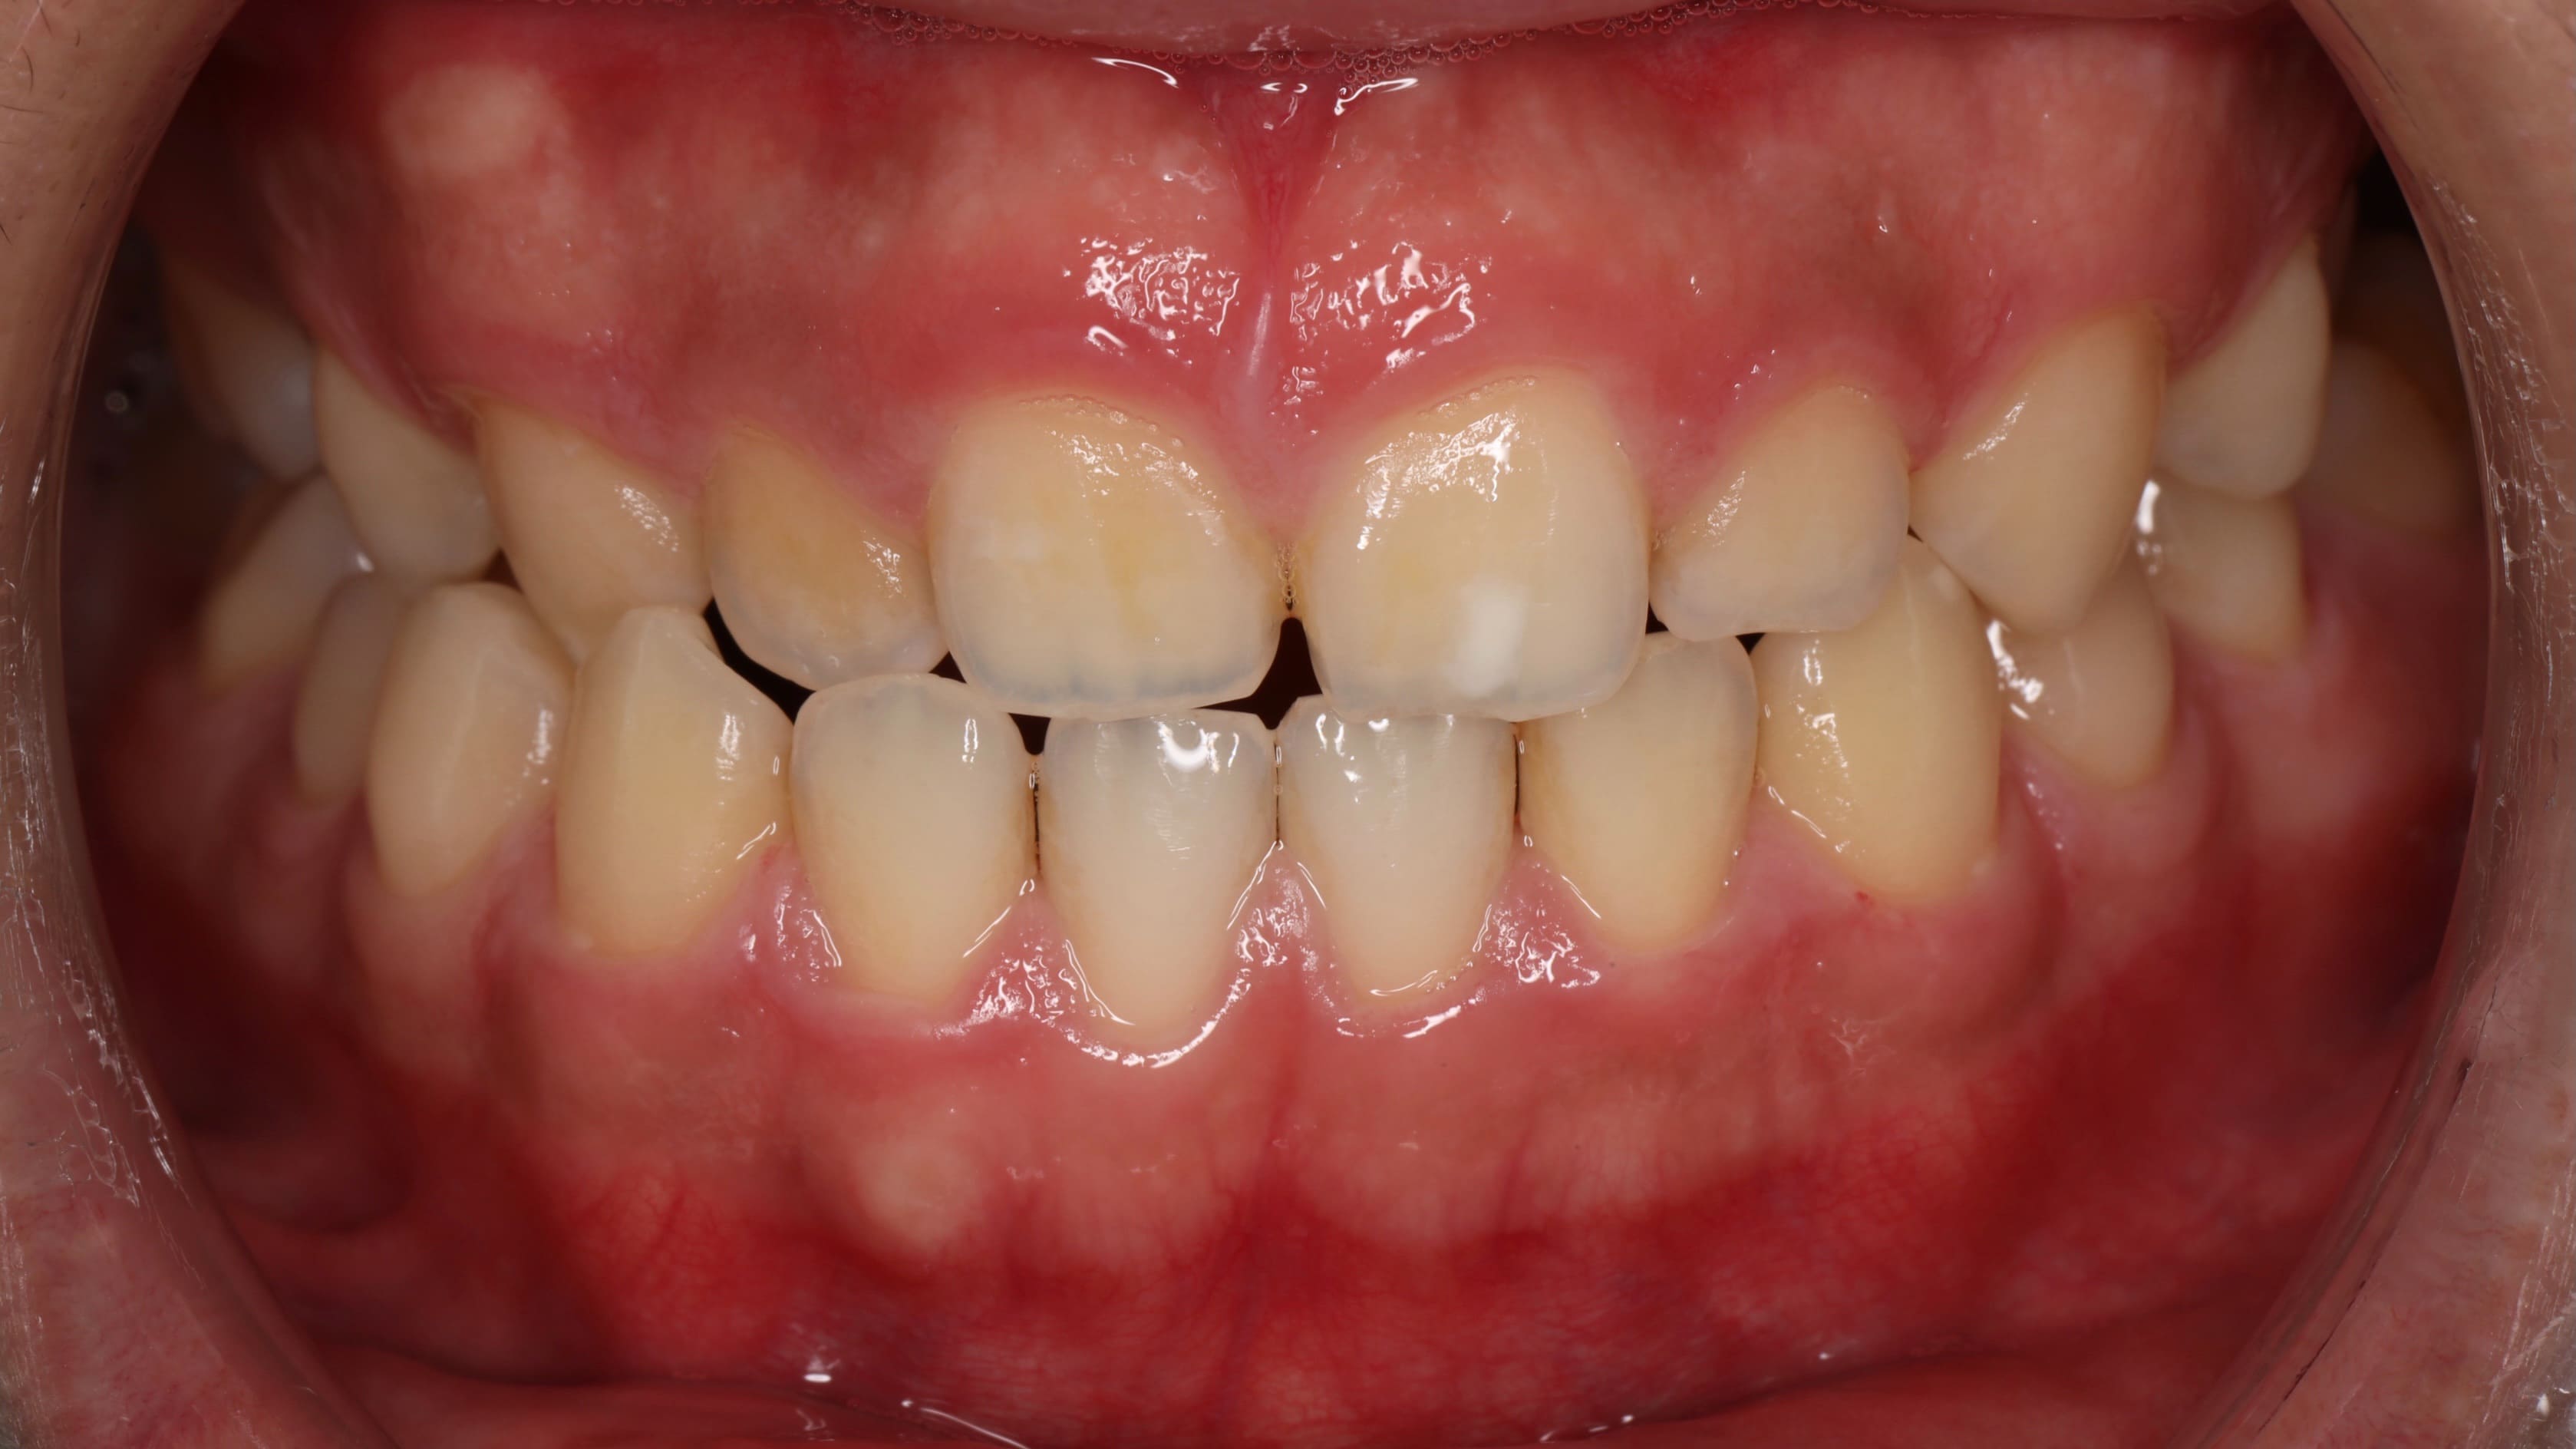

針對這些問題,我們擬定了完整的治療方案。首先,利用矯正的方式,將後方的第二大臼齒和智齒慢慢往前移動,填補缺牙的空間,同時調整上下排牙齒的咬合關係,讓錯咬的情況回復到正常的咬合狀態。當矯正治療完成後,病患的狀況其實已經改善了許多。

為了讓笑容更加完美,我們接著運用雷射方式進行微創的牙冠增長術,調整前牙美觀區牙齦的高度,讓牙齦和牙齒的比例更協調,整體笑容線條也更加自然。

完成所有療程後,病患的笑容真的煥然一新!不僅外觀上有了明顯的改變,整個人也變得更愛笑、更有自信了。